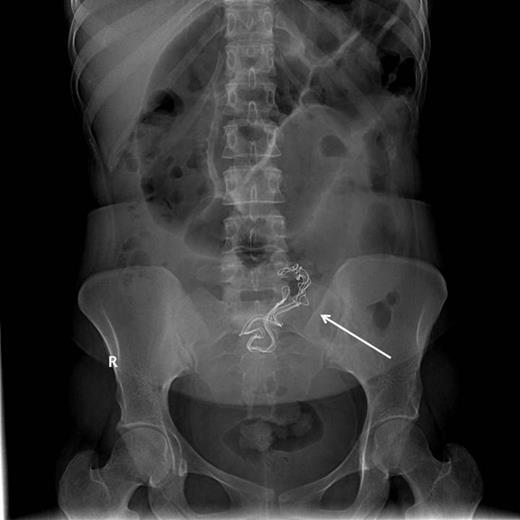

Upon admission, she was afebrile, vitally stable, and her abdomen was distended and tympanic. Bowel sounds were increased in frequency and pitch. Digital rectal examination showed normal-colored stool. Laboratory investigations showed a white blood cell count of 10 700 cells/ml and a sodium level of 123 mmol/l, while other biochemical parameters were within normal limits. Abdominal roentography revealed dilated small intestinal loops with a finding of a radio-opaque density in the abdomen (Fig. 2). A diagnosis of small intestinal obstruction most likely caused by retained surgical sponge was made. On abdominal exploration, the small intestine was dilated down to the ileum with an intraluminal mobile mass felt in the distal ileum (Fig. 3). Before proceeding for mass removal, at around 80 cm from the duodenojejunal junction, there were two adjacent segments of the jejunum adherent to each other and both were adherent to the peritoneal wall by fibrous adhesions. Consequently, adhenolysis, enterotomy and removal of the mass, which was manually pushed there (Fig. 4), followed by resection and anastomosis of the compromised jejunal segment, were achieved. The foreign body was found to be retained surgical sponge (Fig. 5). However, apart from the isolated area of adhesion, exploration of the rest of the abdominal cavity did not show any lesions in the peritoneal cavity or perforation or fistula or pelvic collection. The authors concluded that the transluminal migration of the sponge most likely occurred from that adherent part of the jejunum. The postoperative period was uneventful and the patient was discharged on the seventh day of her hospitalization in good condition.

Intraoperative removal of the foreign body from the jejunum (arrow).